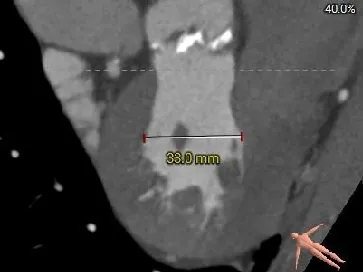

AAO

42.4mm

升主扩张